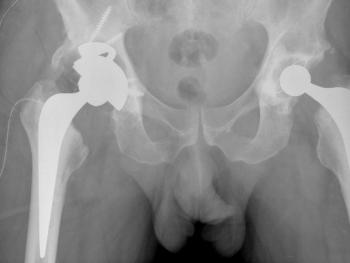

Clinical cases: variations of Exeter stem size and offset copes with almost all abnormal anatomies.

Figure 7 & Figure 8: DDH case with bowed femur and over-riding GT.

Figure 9 & Figure 10: DDH case – small socket – 40/22mm required. Leg length restored. Modularity of head sizes and offsets allows accurate restoration of leg length and offset.